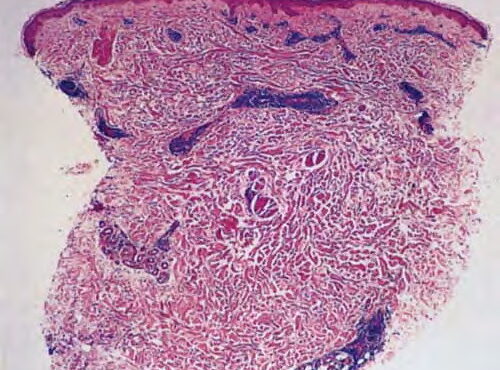

Epidermolysis bullosa acquisita = انحلال البشرة الفقاعي المكتسب Epidermolysis Bullosa Acquisita Classically, EBA is a noninherited disorder of acquired skin fragility. This presentation of EBA was the only one recognized until later. Blisters develop on noninflammatory bases with a predilection for acral areas. Scarring and milia formation ensue. A characteristic nail dystrophy and alopecia are […]